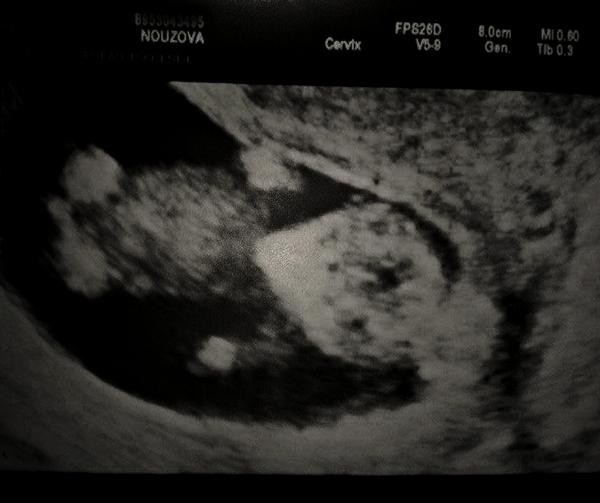

ahojky holky tak vás jdu trošku povzbudit že to jde minulou sobotu sem zase zašpinila tak sem v po šla k dr. a tohle mi vytiskl když sem odcházela vše je v pořádku srdíčko buší žádný hematom tam není takže se asi dočisťuju jinak ted už žádný problém není jen že mám teda bříško jak 20tt takže na vás všechny plivu těhu bacilky at vám to taky brzo vyjde. jinak na screening jdeme 11.2. a 6.2. poradna + prukazku moc se těším